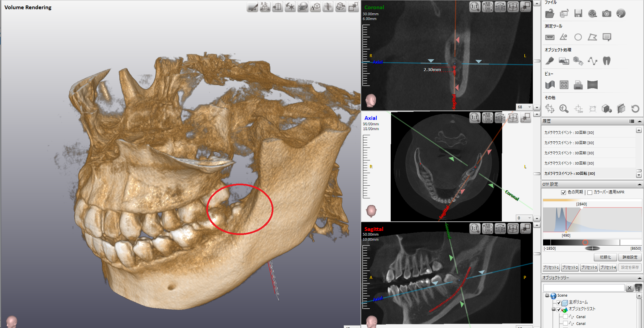

更に詳細を分析します。

赤いチューブのような線は、下顎管といわれる動脈と神経で、親知らずの根の先と、かなり距離が近いです。

CTの角度を変えて、親知らずと下顎管の距離を計測します。

その距離、およそ2.3mm

ここまで下顎管との距離が近いと、親知らずを抜く際に、神経や動脈を損傷するリスクがあります。

神経を損傷すれば、麻痺が残る可能性がありますし、

動脈を損傷すれば、大量出血の可能性があります。

この親知らずの場合は、そこまでの超ハイリスクではないのですが、

親知らずのほとんどが骨に埋まっていることなど総合的に判断すると

「うちで簡単に抜けるよ。」とは言えないレベルです。